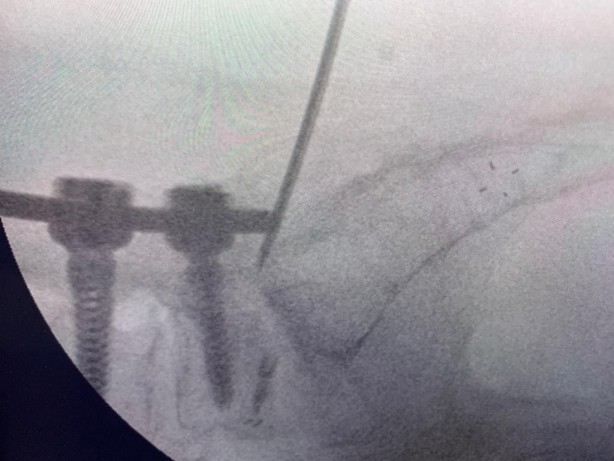

Beyin ve Sinir Cerrahisi Uzmanı Prof. Dr. Kemal Yücesoy, vidalı omurganın kırığına dünyada ilk kez transforaminal transdiskal yaklaşımla sement desteği yaptı. Geliştirdiği yöntem, nöroşirürji alanında dünyanın en prestijli dergilerinden olan World Neurosurgery'nin son sayısında yayımlanarak literatüre girdi. Hastaların sadece 5 dakikasını alan ve 2 saat sonra günlük hayatına dönmesini sağlayan yöntem, Türkiye’ye gurur yaşattı.

Uzun süre, vidayı çıkarmadan kemik çimentosunu koyma konusunda çalışmalar yaptığını belirten Prof. Dr. Yücesoy, “Kapalı bel fıtığı ameliyatlarında iğneyle sinirin altına girerek izlediğimiz bir yol var. ‘Hastaların kemiğinin içine bu yoldan girilebilir’ diye düşündüm ve bunu da uygulamaya başladım. Bu yöntemde, hastaya lokal anestezi uyguluyoruz. Kıkırdağın olduğu bölümden diskin içine iğneyle girip oradan da kemiğin içine ulaşıyoruz ve çimentoyu koyuyoruz. Bu daha önce hiç uygulanmamış bir yol. Kırılmış vidalı bir kemiğe ilk kez o vidayı çıkarmadan kapalı yöntemle girip müdahale etmiş olduk” diye konuştu.